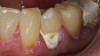

Case Study 2

A 45-year old male patient presented with tooth No. 21 that had an intermediate restorative material (IRM) restoration on the facial aspect after a pulpotomy due to a carious lesion into the pulp from the facial (Figure 7 and Figure 8). The patient had root canal therapy and a post-and-core buildup placed on No. 21 before the crown. The patient was involved in the decision-making for the enamel shade on No. 21. He wanted to make sure that the clinicians did not match No. 21 with No. 20 because he felt the shade on No. 20 was too dark. Instead, the patient wanted to match the new ZLS that had been planned on No. 21 with the natural shade of No. 23 and No. 24. The facial and occlusal views revealed the obvious differences in shade between No. 21 and No. 20. The plan was to use pressable ZLS due to its esthetics, shade-matching abilities, strength, and ease of finishing, so it was decided to involve the dental laboratory technician with the shade-taking process. In planning the discussion with the laboratory technician, the author felt that the best shade would be a Vita A3.5. However, because the laboratory technician worked about 90 minutes away, the author wanted to get his input on the shade by sending him several photographs using the shade the author felt tooth No. 21 was (ie, Vita A3.5) plus shades that were close (ie, Vita A3 and Vita A4). Laboratory technicians are more familiar with shading techniques and may see something that the dentist did not see in the surrounding teeth. This is important when using ZLS to take full advantage of the blending ability that this material displays. The final crown displayed a vibrant match of hue and chroma (Figure 9 through Figure 13).